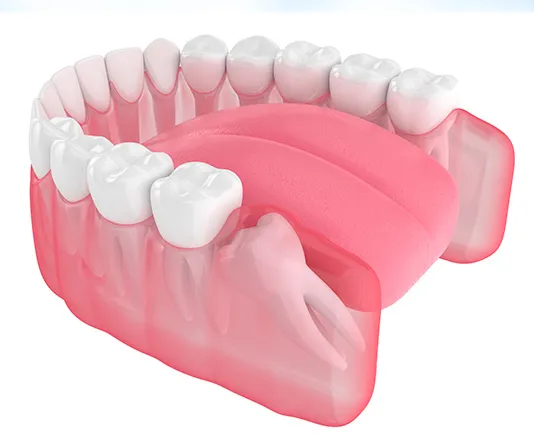

Dental implants provide a permanent, natural-looking solution for missing teeth. The implant is surgically placed in the jawbone, where it fuses with the bone for a secure and long-lasting fit. Implants help maintain bone density, restore function, and enhance aesthetics. With proper care, they can last a lifetime.